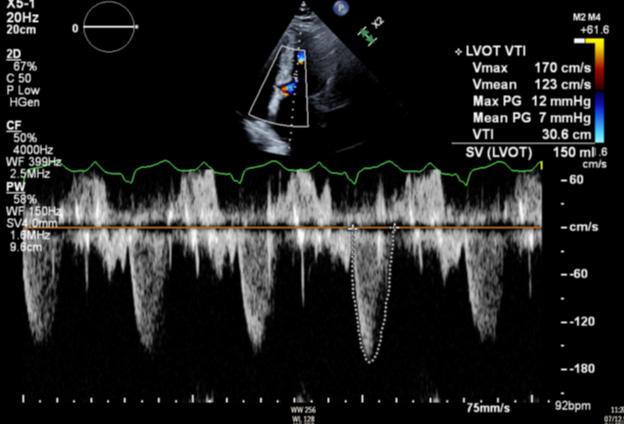

Figure 1: Vista coronal de resonancia magnética cardíaca IVS engrosamiento 3,0cm e infiltración fibrosa septal.

INTRODUCCIÓN

• La miocardiopatía hipertrófica (MCH) es una enfermedad cardíaca genética autosómica dominante, caracterizada predominantemente por hipertrofia ventricular izquierda (HVI) secundaria a mutaciones genéticas que codifican proteínas del sarcómero cardíaco.

• Esta mutación puede conducir a un gradiente del tracto de salida del ventrículo izquierdo (TSVI) de más de 30 mmHg causando obstrucción del TSVI en hasta el 75% de los pacientes con MCH.

• La terapia de reducción septal se ha reservado para pacientes sintomáticos con gradiente de más de 50 mmHg refractario a la terapia médica. Sin embargo, el tratamiento farmacológico con Mavacamten, el inhibidor alostérico de miosina cardíaca primero en su clase, obtuvo recientemente la aprobación de la FDA debido a una mejora significativa del gradiente TSVI y mejoría de los síntomas.

CASO

• Hombre hispano (puertorriqueño) de 39 años con antecedentes de dislipidemia e hipertensión arterial que

desarrolló disnea al realizar actividad física.

• Estaba hemodinámicamente estable y el examen físico fue notable para un II/VI soplo sistólico que se escucha mejor a través del RUSB y LLSB.

• El ecocardiograma realizado para evaluar la función y las estructuras cardíacas, reveló fracción de eyección conservada, engrosamiento del tabique interventricular de 2,9 cm y gradiente del TSVI de 48 mmHg.

• La resonancia magnética cardíaca

Cardiovascular Disease Fellowship Program, St. Figure 2: Vista sagital de la resonancia magnética cardíaca IVS engrosamiento de 3,0 cm e infiltración fibrosa septal.

posterior mostró un engrosamiento del tabique interventricular de 3,0 cm, así como una infiltración fibrosa del tabique confirmando el diagnóstico de MCH.

TOMA DE DECISIONES

• Se inició la terapia establecida por guías médicas y se colocó desfibrilador cardioversor implantable como prevención primaria de muerte súbita cardiaca.

• En vista de síntomas persistentes congruentes con la New York Heart

Association (NYHA) clase II, a pesar de terapia óptima establecida por guías médicas, el paciente se inició en Mavacamten.

• La visita de seguimiento a las 8 semanas de su inicio demostró síntomas mejorados consistentes con la clase I de la NYHA, ausencia de soplos audibles y evidencia de reducción del gradiente del TSVI a 7 mmHg.

CONCLUSIÓN

•La terapia de reducción septal se

ha considerado la terapia principal para reducir el gradiente y los síntomas de TSVI, sin embargo, los resultados dependen del operador y están limitados por el acceso a centros de atención terciaria capaces de realizar estos procedimientos invasivos.

• El auge de Mavacamten puede proporcionar un cambio a una alternativa no invasiva, mejorando la accesibilidad y reduciendo las complicaciones quirúrgicas en el manejo de la MCH avanzada.

Figure 4: Deformación miocárdica longitudinal del ecocardiograma basal. Figure 5: Ecocardiograma 8 semanas después del uso de Mavacamten que muestra un gradiente en el TSVI reducción de 48 mmHg a 7 mmHg. Figure 6:Ecocardiograma 12 semanas después del uso de Mavacamten que muestra una continua reducción del gradiente del TSVI a 3 mmHg.